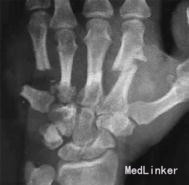

入院检查左手背皮肤自腕部向掌指关节背侧潜行剥脱,呈大小约6cm×4cm的创面,创面污染重,软组织挫裂重,可见部分背伸肌腱、掌骨、骨间肌及掌背血管外露,血管可见大段栓塞。活动性出血明显,左手掌自腕部尺侧斜行向近侧掌横纹远端挫裂,创面不规则,大小鱼际肌、掌腱膜、肌腱外露,尺侧损伤尤重,左手各指除拇指外感觉减退或消失,第2~5指背伸活动消失,环指远节指间关节屈曲障碍,中指、小指远节指间关节屈曲消失。掌指关节及近节指间关节可部分活动。各指远端皮温低,血运差,毛细血管充盈时间延长。左腕部、前臂、肘后肿胀,肘后可及3cm×4cm的血肿。左桡骨下段压痛明显,可触及骨擦感。左肘关节及腕关节活动部分受限。 X线片示左手第2~5掌骨骨折,错位明显,软组织肿胀,左桡骨下段横形骨折。

入院诊断左手损伤,左第2~5掌骨开放性粉碎性骨折,左第2~5指伸肌撕脱损伤,左手背软组织挫裂伤伴缺损,左中、小指指深屈肌腱断裂,左环指指深屈肌腱撕脱损伤,左手骨间肌、蚓状肌断裂、挫裂伤,左手指掌侧总神经、指背侧总神经及指神经断裂,左手指掌指总动静脉、掌浅弓、掌深弓断裂,左手掌软组织挫裂伤,左大小鱼际肌部分断裂,左桡骨下段横形骨折,左肘部软组织损伤。入院后给予急诊清创固定1周后左小指、环指缺血坏死,再次手术行左环、小指切除,左第5掌骨切除、左第4掌骨残端修整、左桡骨下端切开复位固定术,左第2、3掌骨骨折端术后5个月无愈合迹象。术后X线片提示:骨折断端存在间隙,骨痂很少或无,断端分离,髓腔封闭,骨质疏松,无骨小梁形成,符合骨折不愈合诊断。